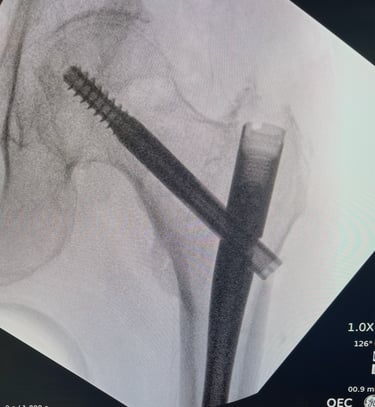

Mi occupo del trattamento traumatico sia in forma conservativa sia chirurgica. Tratto fratture, lussazioni, lesioni dei legamenti e dei tendini, con l’obiettivo di ripristinare la funzionalità articolare, ridurre il dolore e favorire un rapido ritorno alle attività quotidiane e sportive.